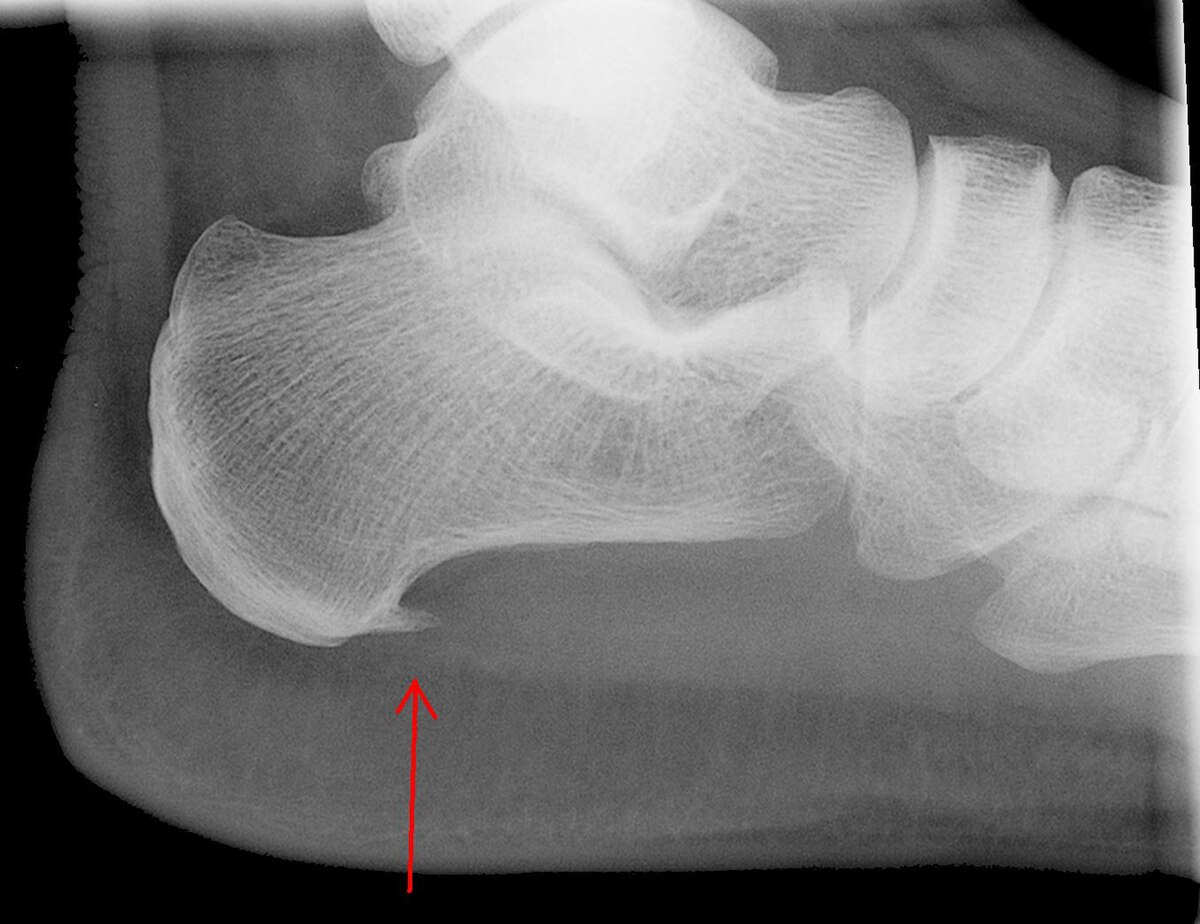

Vid långvarig irritation i övergången mellan sena och skelett kan ett benutskott bildas på undersidan av hälbenet. Detta kallas i folkmun för hälsporre.

Många personer har hälsporre på röntgen utan att ha ont

Hälsporre är ofta ett tecken på en tidigare eller pågående belastningsproblematik, inte orsaken till smärtan.

Röntgen används främst för att utesluta andra tillstånd, som stressfraktur. Förekomst av hälsporre på röntgen förändrar inte behandling eller prognos.